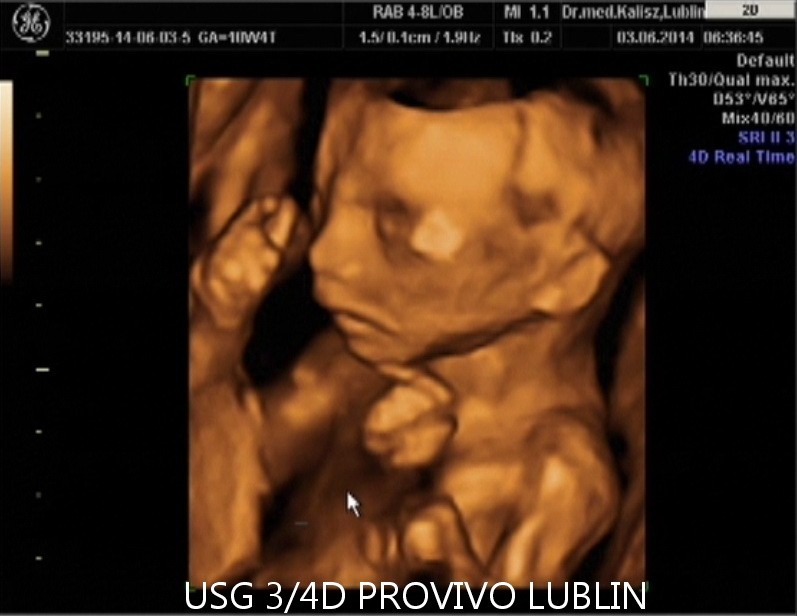

USG 3D daje możliwość trójwymiarowej rekonstrukcji obrazu płodu oraz wnętrza macicy. Dzięki temu można zobaczyć powierzchnię zewnętrzną ciała dziecka, a twarz płodu staje się znacznie wyraźniejsza niż w klasycznym badaniu 2D. To badanie szczególnie cenione przez rodziców, którzy chcą zobaczyć dziecko jeszcze przed porodem w bardziej realistyczny sposób. Na obecnej stronie PROVIVO wskazano również, że rodzice otrzymują zapis badania w formie elektronicznej.

USG 4D Lublin – obraz dziecka w czasie rzeczywistym

USG 4D pokazuje obraz podobny do badania 3D, ale dodatkowo rejestruje go w czasie rzeczywistym. Oznacza to, że rodzice mogą obserwować ruchy dziecka, mimikę twarzy i zachowanie płodu niemal jak podczas podglądu na żywo.

Na stronie PROVIVO wskazano, że badanie może być wykonane między 11. a 14. tygodniem ciąży, a następnie około 20. lub 30. tygodnia ciąży. To właśnie w tych okresach można uzyskać wartościowe obrazy płodu i lepiej ocenić jego rozwój.